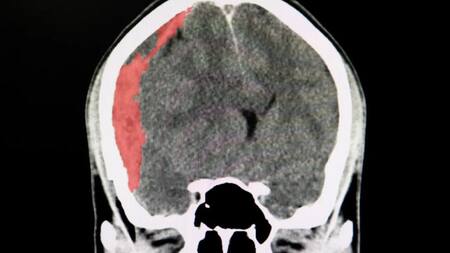

HEMATOMA SUBDURAL CRÓNICO.

El hematoma subdural crónico se da entre la duramadre y el cerebro, y se pueden presentar por traumatismos de cráneo, algunos banales o por una desaceleración brusca, y se presentan en la parte externa del cerebro muchas veces en pacientes anticoagulados o antiagregados.

En sí son como pequeñas venas que sufren una ruptura en la superficie del cerebro, pasa desapercibido y el hematoma con el tiempo progresa por la propiedad oncótica de la sangre que atrae líquido.

El tratamiento a seguir es el drenaje a través de dos agujeros de trepano e incluye un lavado del espacio subdural y luego dejar un drenaje para evitar que la sangre vuelva a formarse.

Al principio el paciente puede sentir dolor de cabeza u obnubilación y hasta movimientos realentizados, incluso puede tener reacciones un poco más lentas y trastornos psiquiátricos.

Si bien la operación no es compleja, se le realiza al paciente dos "agujeritos", y se lava con solución fisiológica, para que el drenaje permita que el cerebro se expanda y se pegue a la tabla interna.

En general, el post operatorio demanda dos días de internación en terapia intensiva, ya que a veces ingresa un poco de aire luego de la hematoma y eso debe reabsorberse.

Lo que se espera es que el cerebro se reexpanda y resolver la hipertensión endocraneana.